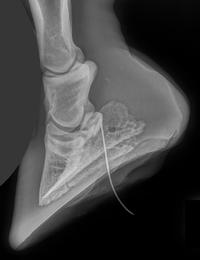

When first presented with the horse and its wound, taking a full history is important. Often owners have no idea how the wound occurred but there are occasions when they witnessed the injury. Factors like impaling on objects such as nails or spikes will help to determine the possible depth of wounds and whether a joint has been breached. Initially, perform a quick clinical examination to determine if the horse has any systemic involvement such as pyrexia. Next, assess the degree of lameness - horses with established joint infections are normally moderately to severely lame. Inspect the wound carefully for evidence of a clear/yellow sticky discharge coming out and running down the limb? This may be joint fluid, but there often will be a serous inflammatory discharge from the wound surfaces. The differentiation between inflammatory discharge and synovial fluid can be difficult but synovial fluid tends to be stickier and more globular compared to the waterier inflammatory discharge. If you gently flex or extend the joints near the wound this may pump out joint fluid and you may see synovial fluid – sometimes bubbly – egress from the wound. For a close inspection the horse will probably require sedation. Clip and clean the wound edges well before investigating the wound. Lavage out the wound with an isotonic fluid like lactated ringers to remove as much foreign material as possible. Retract the wound edges. Any sight or glimpse of white shiny articular cartilage indicates a joint breach. Next, investigate using a blunt ended instrument such as haemostat or small curette, or using a gloved finger, to determine the depth and direction of the wound. If injuries have occurred when the limb was flexed then the skin wound can be in a different position to the joint, so try to find the direction of the wound path that may require the limb being flexed and extended again. Check to feel any smooth hard surface of joint cartilage. Look and feel for any foreign bodies like pieces of wood which might be in the joint. At this stage radiography can be useful to show any damage to joint and bone structures and to outline radio opaque material like metal or wood near the joint. It may also show up air within the joint indicating joint breach, but be aware of any overlying subcuticular emphysema. If there is a penetrating tract detected, radiographing the wound with a probe in place can demonstrate its proximity to the joint. This is especially helpful with puncture wounds to the foot (Figure 1). If you are suspicious of a joint breach, then it may be possible to perform synoviocentesis of any local joint. This is easier in certain joints that have two or three easily accessible sites for synoviocentesis. Care should be taken in doing this if the area around the joint is inflamed and swollen. Apart from swelling making the joint harder to find, if you inject a needle through an inflamed area, local material and bacteria can be iatrogenically introduced into the joint. If this procedure is to be undertaken, then pre-preparing the necessary equipment saves valuable time when you are gloved up (Figure 2). Consider trying to obtain a joint fluid sample for cytologic examination and protein content, and for possible culture. You should also prepare several syringes of isotonic fluid to use as lavage. Regional anaesthesia can facilitate these procedures.

Figure 1: Lateral foot radiograph taken with sterile catheter inserted through a tract from a distal limb wound showing proximity of the wound to the coffin joint.